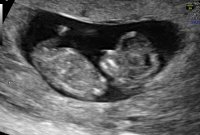

Termindato på meg i morgen, men frøkna er født for 6mnd siden. Jeg skulle visst bare bli englemamma til ei jente, for i magen boltrer det seg en lillebror :Heartblue

Og jeg er evig takknemlig for at alt ser helt perfekt ut på UL i dag med skikkelig anatomisk gjennomgang, fra hodet til tær, og alt som var fryktelig galt er helt perfekt nå. Er 12+2 i dag, men jordmor målte meg til 12+4, så termin rundt 28 april. Spent på om sykehuset finner det samme på ultralyd neste onsdag. Enn hvor glad jeg er for at jeg har en frisk lillebror i magen, så er jeg ett lite snev skuffet. Skuffet over at jeg ikke får min lille prinsesse Maja, som jeg alltid har drømt om. Vet at jeg blir like glad i lillebror som jeg er i storebror og gutt kan jeg jo, men jeg drømte liksom om å få en jente. Men min jente var syk…

Klarer ikke helt å bli klok på mine egne følelser og må nok bruke litt tid på å innse at jeg bare blir guttemamma:Heartblue